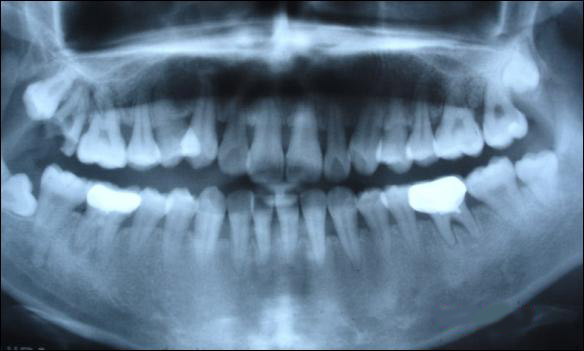

上圖為健康人的全口曲面斷層片,俗稱骷髏片